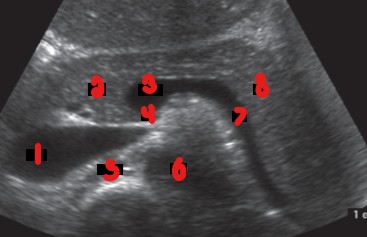

What are the labeled numbers pointing to?

Gastroduodenal artery

Common bile duct

Label the structures with the colored arrows/circle.

Red = GDA

Orange = CBD

Yellow = Portal confluence

Green = Splenic vein

Blue = Uncinate process

Purple = IVC

Pink = RRA

White = LRV

This image was taken in what plane?

Explain your answer.

Transverse

The entire pancreas is visualized